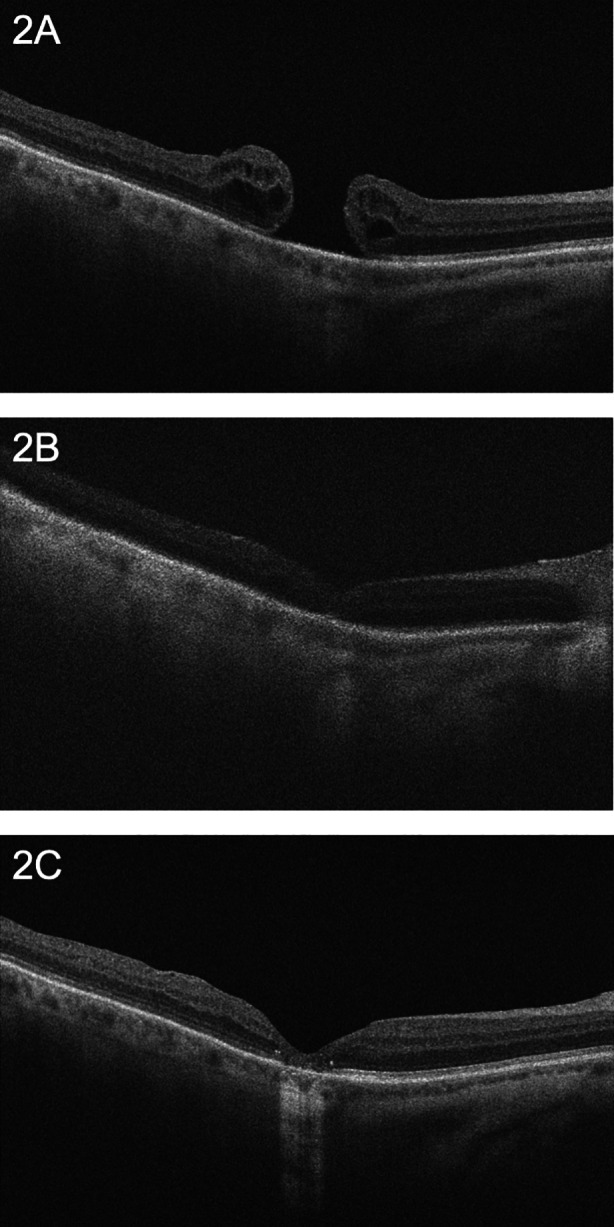

A 68-year-old Caucasian man presented for a second opinion for a persistent MH in his right eye. He had decreased vision for 2 months prior to undergoing pars plana vitrectomy with membrane peel and SF6 gas endotamponade. After the MH failed to close, he underwent repeat pars plana vitrectomy, membrane peel, and C3F8 gas endotamponade, which also failed to close the hole. He subsequently presented to the Cole Eye Institute with a vision of 20/200. An OCT revealed a full-thickness MH with a base diameter of 910 µm and minimum diameter of 470 µm (Fig. 2A). He underwent cataract surgery with intraocular lens placement, pars plana vitrectomy, an ILM flap, and C3F8 gas endotamponade. One week after surgery, an ILM flap was visible over a closed MH (Fig. 2B). The hole remained closed 8 months after surgery and vision improved to 20/50 (Fig. 2C).

Fig. 2.

FTMH closure after ILM flap